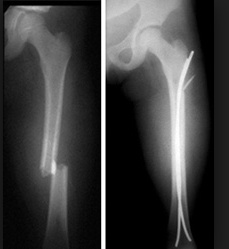

Femur

Femur fractures involve the shaft of the femur and are considered an orthopedic emergency.

Femoral shaft fractures are generally the result of a high-energy trauma.

Femoral shaft fractures are treated surgically, which can include intramedullary nailing or open reduction internal fixation with plating.

These patients are at risk for significant blood loss,compartment syndrome, and fat embolism.